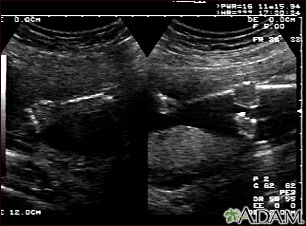

In some cases, a pregnancy ultrasound may be done by placing the probe into the vagina. This is more likely in early pregnancy. Many women will have the length of their cervix measured by vaginal ultrasonography around 20 to 24 weeks of pregnancy.

A pregnancy ultrasound may also be done in the second and third trimesters to:

- Look for twins or triplets. Look at the placenta, amniotic fluid, and pelvis.

Ultrasound may also be performed to guide certain diagnostic procedures in the first and second trimesters to test the placenta and amniotic fluid for certain genetic disorders.